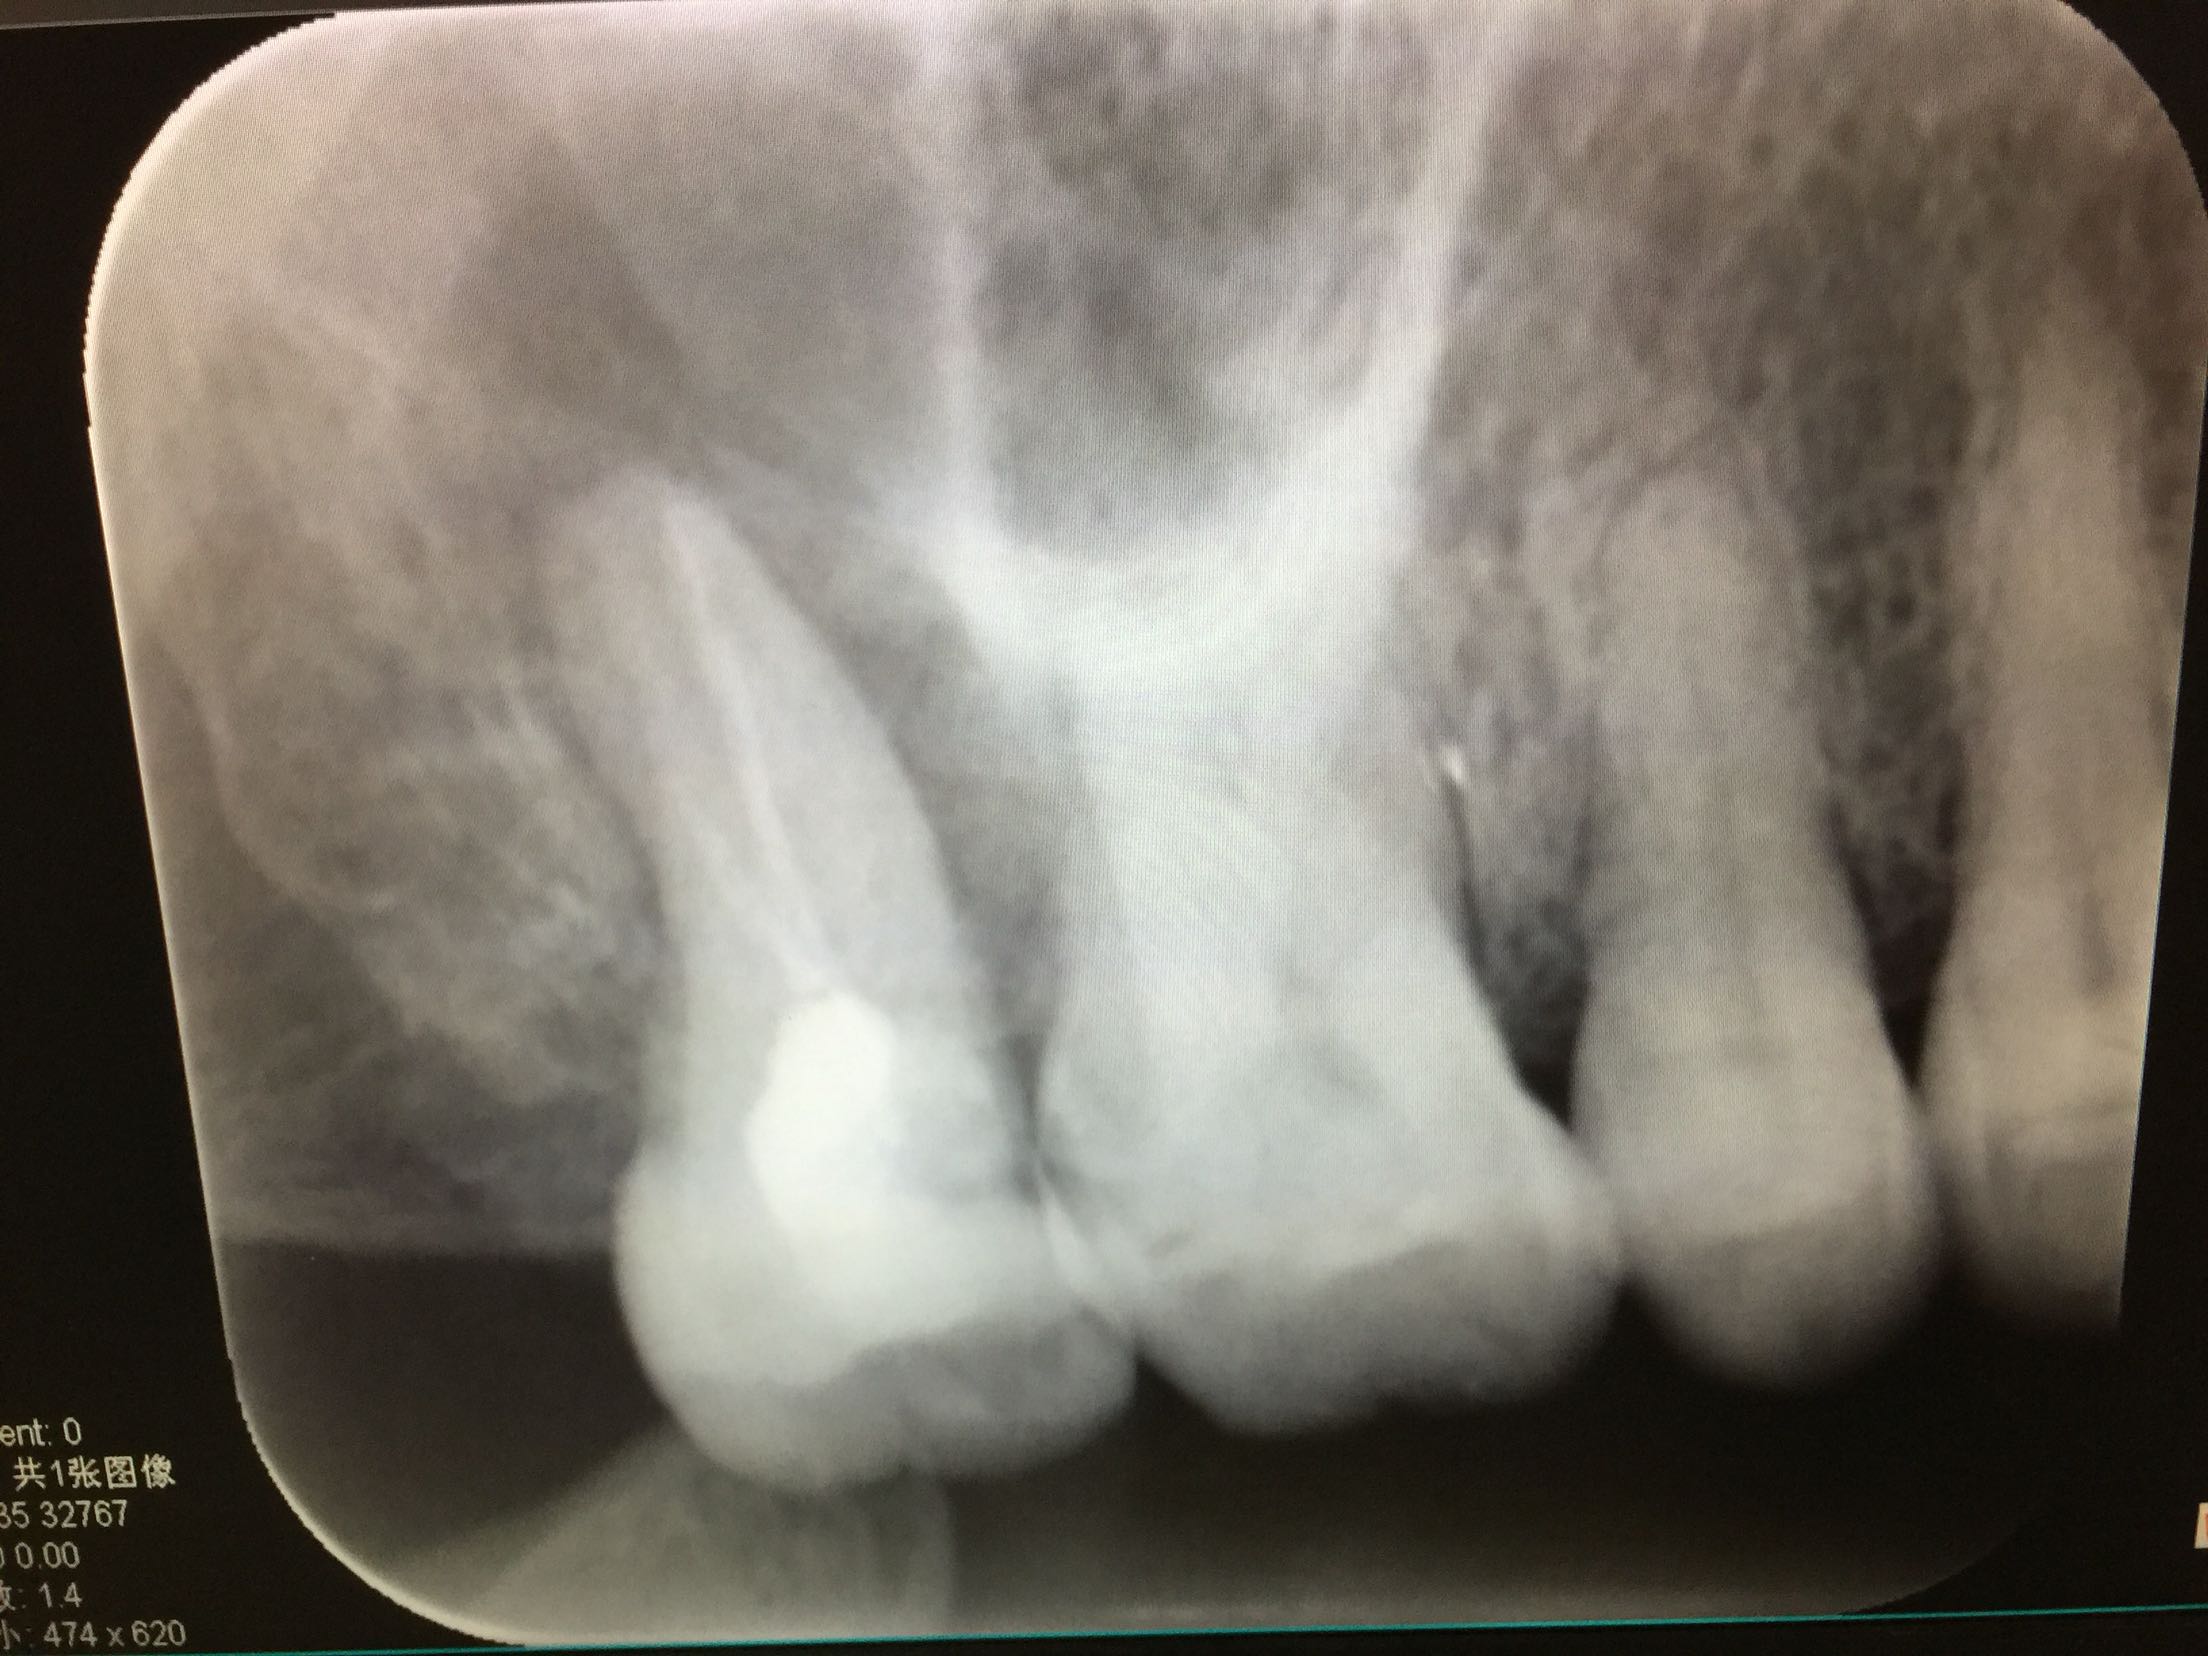

检查 17牙合面可见树脂补物,无继发龋。冷-,探-,叩++,不松。全口卫生差,全口牙龈不同程度退缩。 X线示:17牙已行根管治疗,根充不完善,很尖有暗影。

诊断:17牙根尖周炎 治疗计划:全口龈上龈下洁治术 17牙试行根管再治疗+冠保护 治疗. 17牙去除原补料,探查根管口,双根管,用氯仿溶解原牙胶,清扩,消毒,内封进口氢氧化钙,一周后复诊。 复诊. 诊间患牙疼痛消失,检查 冷-,探-,叩+-,不松。暂封完好,去除暂封,试主尖,合适,热充,回填。患者要求暂不行冠修复。已向患者交待不做冠保护可能会导致牙齿折裂等情况,患者知情同意。